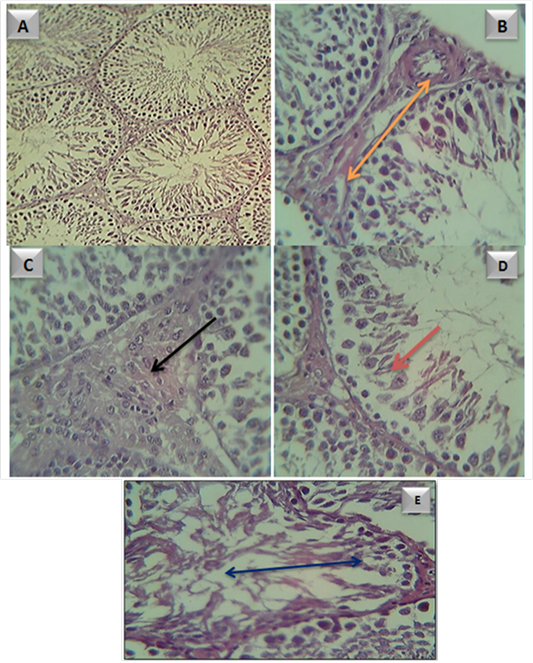

testicular tissue in A- control group. B- adult male rats in (G1) group, showed subcapsular congestion

(). C- adult male rats in (G2) group, showed large and proliferate leydge cells (). D- adult male rats in (G3) group, showed sever atrophic necrosis of spermatogonal cells () E- adult male rats in (G4) group, showed sever atrophic necrosis and distoration of seminiferous tubule ()